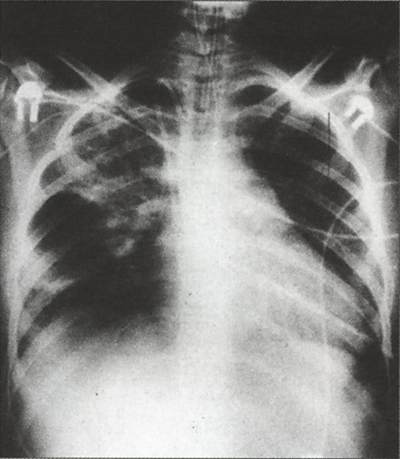

При развитии пневмонии вследствие аспирации инфицированными околоплодными водами во время родов признаки заболевания появляются быстро. Отмечаются побледнение и цианоз кожи, одышка, приступы асфиксии, повышается температура тела. При аускультации вначале появляются сухие, рассеянные, влажные крупнопузырчатые, позднее преимущественно мелко- и среднепузырчатые хрипы. На рентгенограмме обнаруживают инфильтративные тени по ходу бронхиальных разветвлений. Для аспирационной пневмонии характерно скопление аспирирован-ных масс в дистальных отделах дыхательных путей, что рентгенологически определяется в виде множественных очаговых теней, нередко сливающихся в обширные пневмонические инфильтраты. Пневмония нередко сочетается с ателектатическими и отечно-геморрагическими изменениями в легких.

Распознают на основании данных анамнеза о предрасполагающих к раннему инфицированию плода (острые и хронические инфекционные заболевания матери, маточные кровотечения во время беременности и ), факторах ранних клинических признаков заболевания, результатов рентгенологического, бактериологического, вирусологического исследований содержимого дыхательных путей, обнаружении патогенной флоры в околоплодной жидкости.